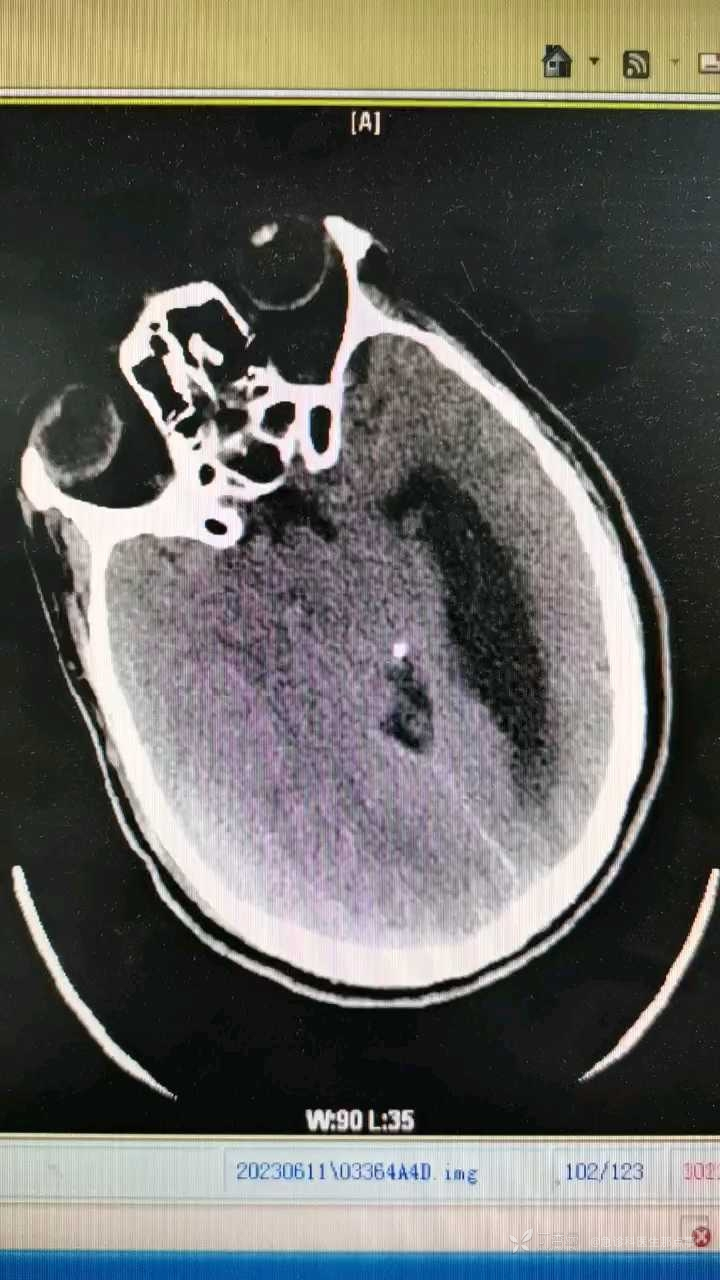

查颅脑CT如下